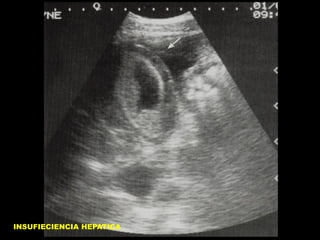

CI HEPATICO CON ASCITIS

INSUFIECIENCIA HEPATICA

INSUFICIENCIA HEPATICA

HEPATIZACION VESICULAR